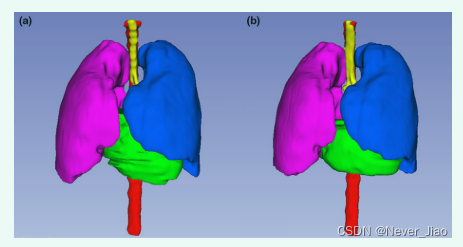

图 3 和图 4 显示了使用所提出的 U-Net-GAN 方法对一名患者进行的 2D 和 3D 分割结果。所提出的方法分割双侧肺、心脏和脊髓,并成功描绘了食道。使用我们的方法获得的 OAR 与ground truth轮廓非常相似。

Fig.4 通过(a)手动轮廓和(b)所提出的方法获得的图 3 中同一患者的风险器官轮廓的 3D 可视化。